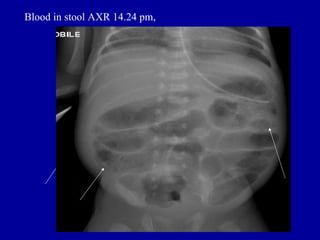

Blood in stool AXR 14.24 pm,

Blood in stoolAXR 14.24 pm,